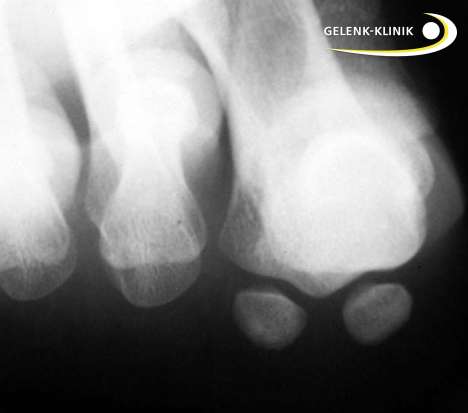

In der Sehne des kurzen Großzehenbeugers (Musculus flexor hallucis brevis) sind zwei Sesambeine eingebettet. Diese kleinen Knöchelchen fungieren als Gleitlager und verstärken die Kraftwirkung des Muskels. Sie liegen unter dem Großzehengrundgelenk und nehmen normalerweise den 1. Zehenstrahl in ihre Mitte.

Beim Hallux valgus sind diese Sesambeine nach außen verschoben. Es entsteht ein Winkel zwischen dem Verlauf des Großzehenstrahls und der Sehne des Zehenbeugers. Je größer dieser Winkel ist, desto ausgeprägter ist die Hallux valgus-Fehlstellung.

In der Folge kann der Patient den Fuß beim Gehen über die Großzehe nicht mehr normal abrollen. Die kleineren Zehen tragen zunehmend mehr Last. Diese Gewichtsverlagerung weg von der Großzehe kann Mittelfußschmerzen (Transfermetatarsalgie) zur Folge haben.